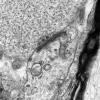

Neuroaxonal dystrophy (3)